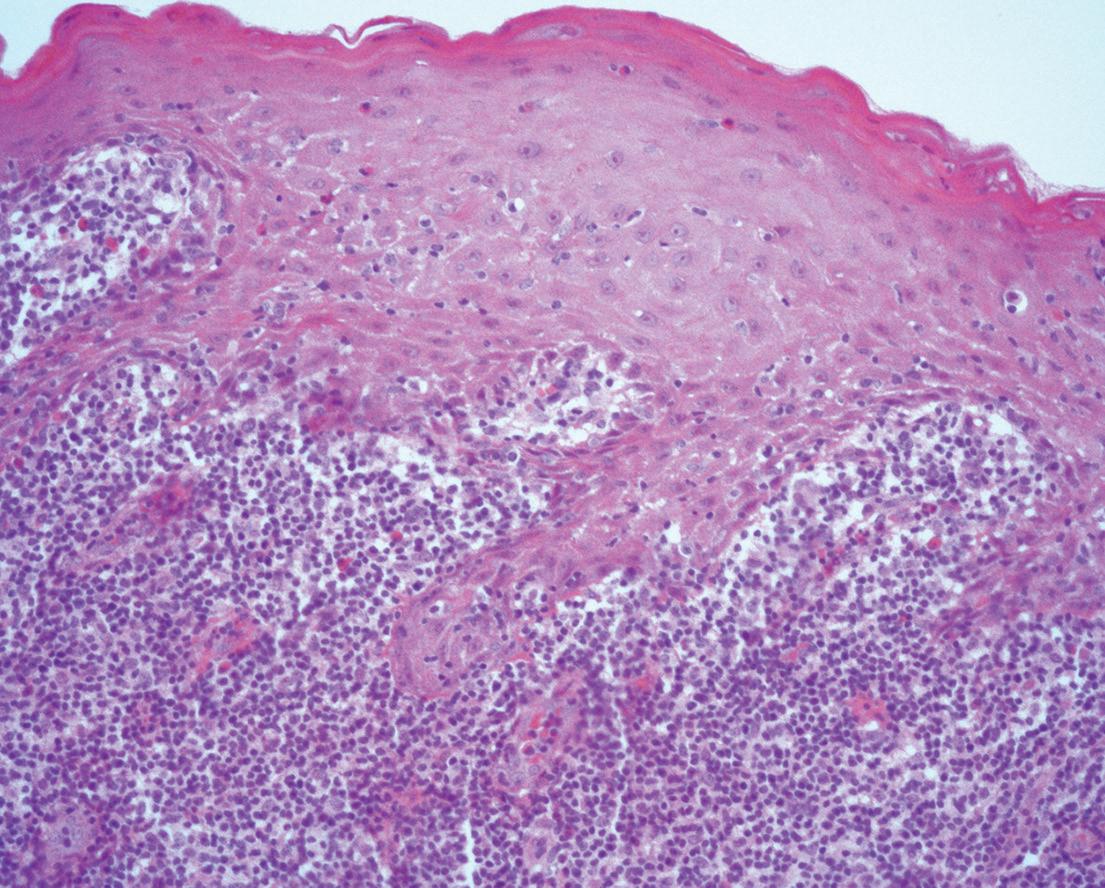

59 Oral Medicine, Oral Diagnosis, Oral Pathology

Malignant transformation of oral lichen planus after 6 years: a case report

Patrícia Peres Iucif Pereira

João Adolfo Costa Hanneman

Henrique de Carvalho Petean

Alessandro Antônio Costa Pereira